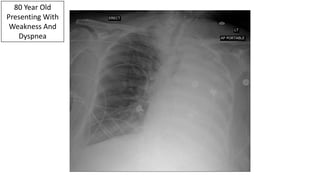

80 Year Old

Presenting With

Weakness And

Dyspnea

Left Mainstem Obstruction: Neoplasm Vs. Mucous Plug

Bronchoscopy Reveal A Mucous Plug